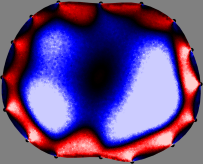

Refer to caption

Figure 2: Fidelity-embedded regularization method. (Left bottom) Correlations between four different column vectors (𝐒ksubscript𝐒𝑘{\bf S}_{k}) and all the remaining column vectors (𝐒subscript𝐒{\bf S}_{\ell}) are visualized. (Right bottom) Performances of the proposed fidelity-embedded regularization method for λ=𝜆\lambda=\infty are shown by numerical simulations.

To explain the FER method, we closely examine the correlations among column vectors of the sensitivity matrix 𝕊𝕊\mathbb{S}, described in Fig. 2. The correlation between 𝐒ksubscript𝐒𝑘{\bf S}_{k} and 𝐒subscript𝐒{\bf S}_{\ell} can be expressed as

for i=1,,16𝑖116i=1,\cdots,16[23]. This shows that the column vector 𝐒ksubscript𝐒𝑘{\bf S}_{k} is like an EEG (electroencephalography) data induced by dipole sources with directions uj,j=1,,16formulae-sequencesubscript𝑢𝑗𝑗116\nabla u_{j},j=1,\cdots,16 at locations ΔksubscriptΔ𝑘\Delta_{k}. Given that two dipole sources at distant locations produce mutually independent data, the correlation between 𝐒ksubscript𝐒𝑘\mathbf{S}_{k} and 𝐒subscript𝐒\mathbf{S}_{\ell} decreases with the distance between ΔksubscriptΔ𝑘\Delta_{k} and ΔsubscriptΔ\Delta_{\ell}. Fig. 2 shows a few images of the correlation 𝐒k,𝐒(|𝐒k||𝐒|)1subscript𝐒𝑘subscript𝐒superscriptsubscript𝐒𝑘subscript𝐒1\left\langle\mathbf{S}_{k},\mathbf{S}_{\ell}\right\rangle(|\mathbf{S}_{k}||\mathbf{S}_{\ell}|)^{-1} as a function of \ell for four different positions ΔksubscriptΔ𝑘\Delta_{k}. The correlation decreases rapidly as the distance increases. In the green regions where the correlation is almost zero, 𝐒subscript𝐒{\bf S}_{\ell} is nearly orthogonal to 𝐒ksubscript𝐒𝑘{\bf S}_{k}.